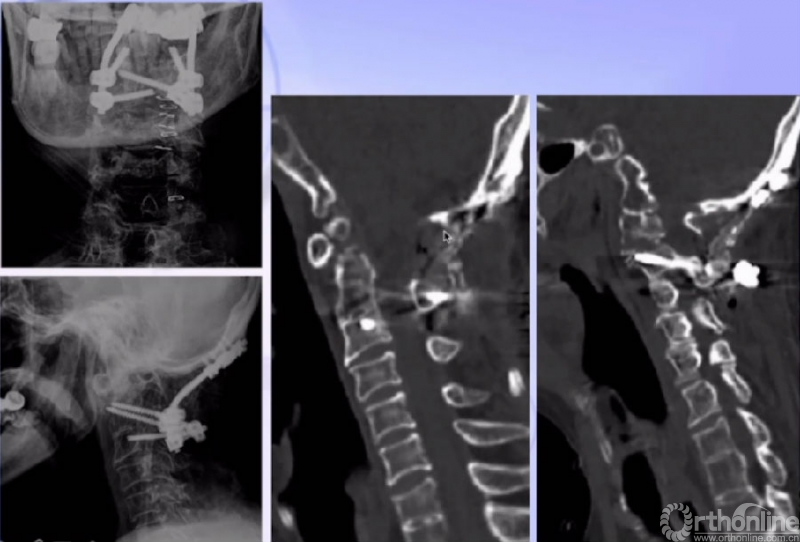

术后CT

术后MRI(患者术后四肢麻木、乏力,发音、吞咽困难改善。)

患者术后未使用无创呼吸机,呼吸功能明显改善,术后3天血气分析恢复至正常范围

单一后路:松解+复位+融合

后弓切除减压 经后路侧块松解

复位、内固定

4. 齿状突复位是治疗难复性寰枢椎脱位最重要的中心环节;

5. 枕颈融合术后,通过有效松解(截骨)仍能使齿状突复位。此类患者首选单一后路手术治疗;部分患者需通过前、后路联合手术进行松解,才能使齿状突获得满意的复位。